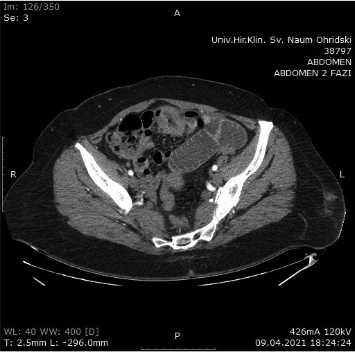

Contrast-enhanced Computerized Tomography (CECT) of the abdomen was the next diagnostics tool. The small intestine was presented with dilated loops, formed “air fluid levels” and free fluid in the Douglas pouch. The tumor formation itself was not detected by the radiologist on this scan (Figure 2).